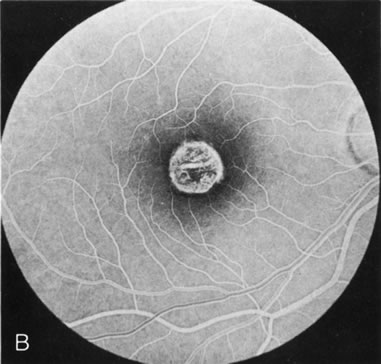

The intact solid yellow egg yolk lesion in Best's vitelliform macular dystrophy (BVMD) typically shows hypofluorescence on FA due to blockage of the underlying choroidal fluorescence with the overlying retinal vasculature visible (Fig. 10A and, B). This finding places the lesion in front of the choroid, possibly within the RPE, but probably not within the neurosensory retina. There is no histopathology of the intact lesion to confirm this.

Fig. 10. Best's vitelliform macular dystrophy. The most characteristic angiographic finding in the solid yellow egg-yolk stage is blocked hypofluorescence (A, B). A morphologically mimicking lesion (pseudovitelliform degeneration) may be the result of leakage from the underlying choroid (C–E).